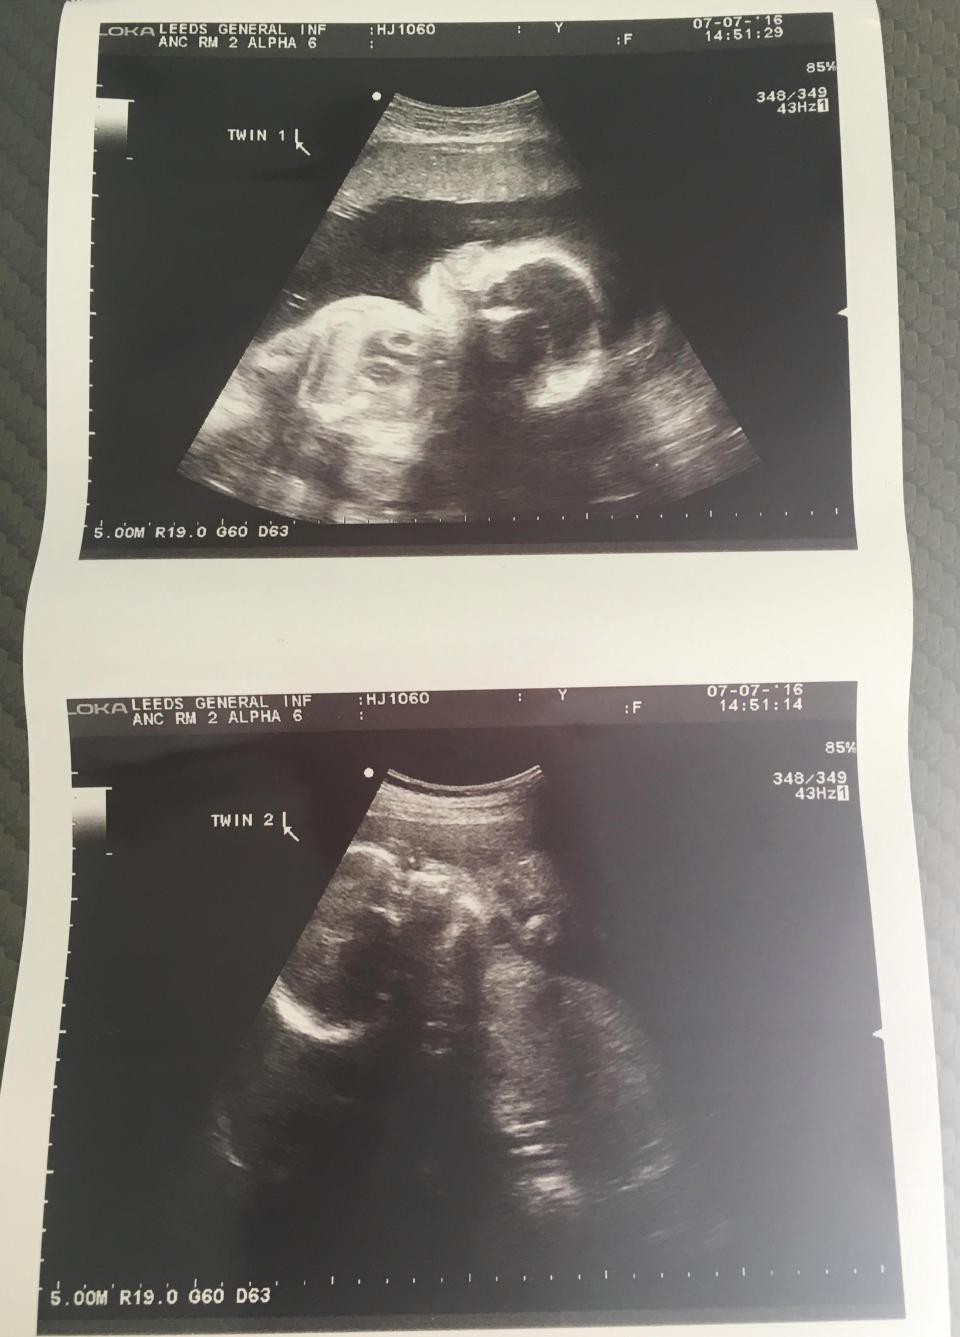

30歲的Amy和32歲的丈夫 Conno,12年前在大學結識,而在2015年9月結婚後。當Amy知道她在2016年2月懷孕時,但在懷孕11週時突然出血,醫生診治後超聲波顯示發現Amy是懷上雙胞胎,他們都感到十分震驚和喜悅。

非同卵雙胞胎有單獨的胎盤和羊膜囊,但懷孕24周的Amy,因 Esme的羊膜囊羊水破裂,再次被送往醫院臥息,而Esme需要與姐姐分享羊水。因為醫生認為雙胞胎姐妹情況不佳,而在27周緊急生產。